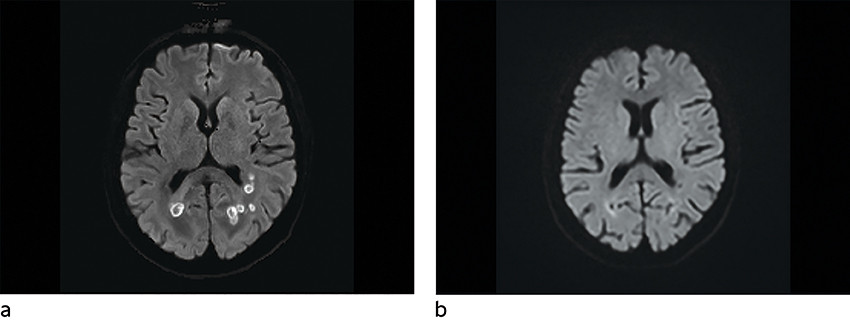

MR caput ble utført om kvelden innleggelsesdagen, ca. ti timer etter at pasienten kom på gastroenterologisk laboratorium. Denne viste multiple runde foci subkortikalt parietooksipitalt bilateralt, med moderat omkringliggende ødem (figur 1, figur 2, figur 3). Lesjonene hadde lavt T2-signal både sentralt og perifert. Det var høy diffusjon sentralt, men en tykk perifer kapsel med betydelig nedsatt diffusjon. Susceptibilitetsvektede sekvenser (SWI) viste signalbortfall både perifert og i punktformede områder sentralt, noe som kunne være blodnedbrytningsprodukter eller paramagnetiske elementer (jern, magnesium, sink, nikkel). Det var lett forhøyet T1-signal i enkelte lesjoner, hvilket også kunne tyde på innhold av blodnedbrytningsprodukter. I tillegg var det en tynn, lobulert kontrastoppladning i periferien av lesjonene, stedvis med uskarpe grenser mot omkringliggende parenkym.

Disse karakteristikaene ved lesjonene hos en immunsupprimert pasient med tegn til infeksjon gav mistanke om soppabscesser, mest sannsynlig forårsaket av Aspergillus sp.

Hjerneabscesser kan ha variable bildediagnostiske utrykk avhengig av agens og utviklingsstadier (4). Man kan ikke bestemme agens ut fra MR-undersøkelse, men karakteristika på standardsekvenser, diffusjonsvektede sekvenser (DWI) og susceptibilitetsvektede sekvenser kan brukes for å skille pyogene abscesser fra soppabscesser (4–6). Av sekvensene synes de diffusjonsvektede å være de mest sensitive for tidlig identifikasjon av cerebral aspergillose (5). Disse er også nyttige i differensieringen mellom soppabscesser og pyogene abscesser (tabell 1) (5). Begge kan vise diffusjonsrestriksjon i hulrom, men bakterielle abscesser har ofte homogen diffusjonsrestriksjon sentralt, i motsetning til soppabscesser, der signalet er inhomogent. Soppabscesser viser også typisk diffusjonsrestriksjon i veggene, noe som er uvanlig ved pyogene abscesser (5). Aspergillusabscesser er ofte multiple, med lobulerte konturer, ujevne indre grenser og variabel kontrastoppladning i periferien (4, 5). På T2-sekvenser og susceptibilitetsvektede sekvenser fremstilles lav intensitet sentralt, grunnet høy forekomst av paramagnetiske elementer (jern, magnesium, sink, nikkel), som er viktig for soppens vekst. Dette er uvanlig ved pyogene abscesser. Ved aspergillusabscesser kan man se hemoragisk nekrose (4, 5).